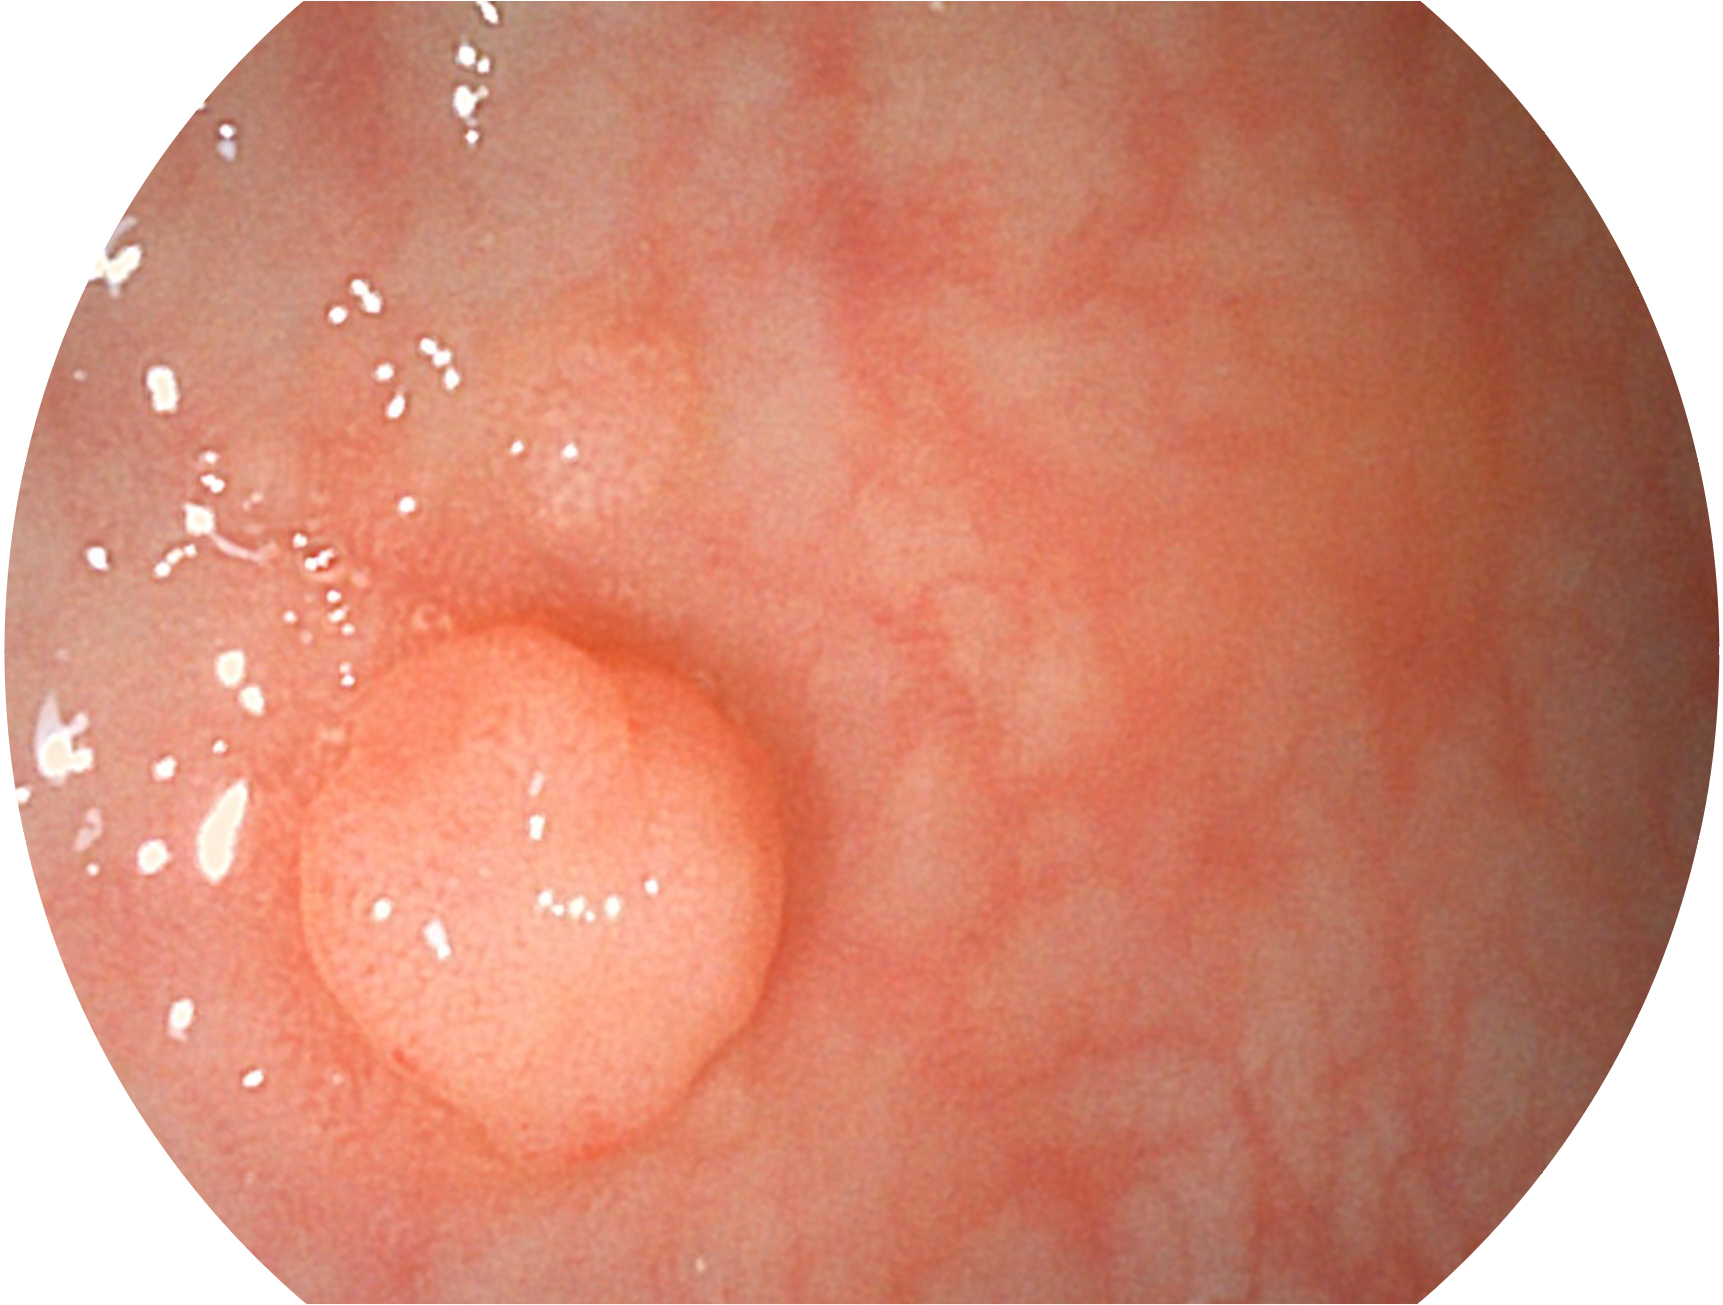

环球UG官网新开发的内镜染色技术,主要是基于多波长LED 光源的开发,VLS-55Q 四波长LED 光源是由四个不同颜色的LED光按照相应照明模式所规定的特定发光比例进行合束后形成,合束后形成的照明光的光谱由红光、绿光、蓝光及蓝紫光这四个不同的波段范围构成。具有更高光谱自由度,通过光谱比例的控制,实现了聚谱成像技术,英文全称为“Spectral Focused Imaging, SFI”,缩写为“SFI”和光电复合染色成像技术,英文全称为“Versatile Intelligent Staining Technology, VIST”,缩写为“VIST”。